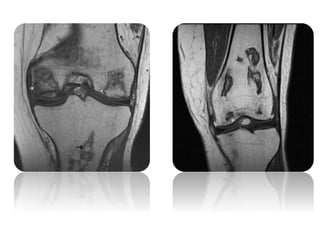

• X RAY

- slight flattening of medial femoral condyle on both AP & lateral views

- MRI

- evidence of well localized osteonecrosis in lateral condyle & extensive

involvement of the medial condyle

- T1 images show decreased signal